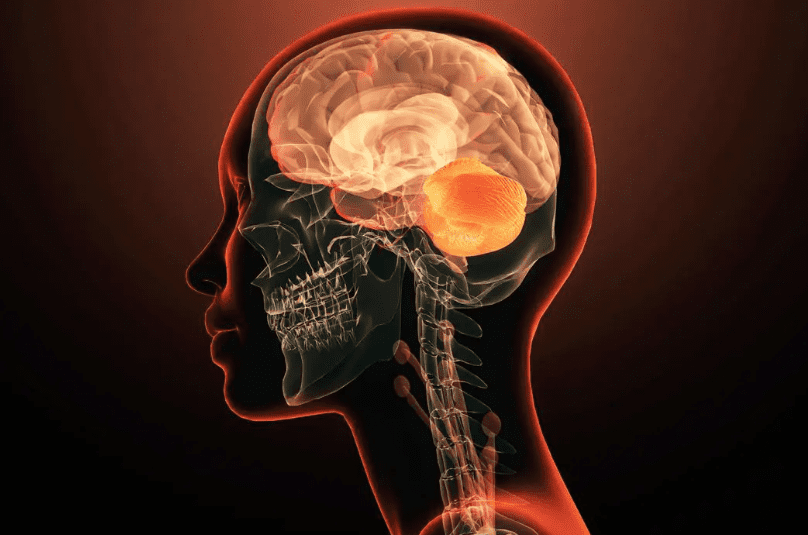

Beyin yağlanması, beynin enerji metabolizmasında yağların anormal şekilde birikmesi veya kullanılmasıyla ilişkili bir durumdur ve son yıllarda yapılan araştırmalar bunun Alzheimer hastalığıyla doğrudan bağlantılı olabileceğini göstermektedir. Beyin yağlanması, aslında organ yağlanmasının bir uzantısı olarak düşünülebilir. Vücutta özellikle iç organlarda ve dokularda yağ birikimi arttığında, bu durum beyinde de metabolik dengesizliklere yol açar. Normalde beyin, enerji kaynağı olarak ağırlıklı biçimde glikozu kullanır; ancak yeni bulgular, nöronların elektriksel aktiviteleri sırasında yağ damlacıklarını da enerji için kullanabildiğini ortaya koymuştur. Bu süreçte yağların aşırı veya yanlış şekilde depolanması, beyinde toksik etki yaratabilen anormal proteinlerin (örneğin beta-amiloid ve tau proteinleri) birikimini kolaylaştırır. Bu protein birikimleri, Alzheimer’ın temel patolojik mekanizmasını oluşturur ve hastalık başlamadan yaklaşık 20 yıl önce beyinde sinyal vermeye başlar. Dolayısıyla beyin yağlanması, Alzheimer riskini artıran önemli bir faktör olarak görülmektedir. Özellikle yaşlanmayla birlikte metabolizma yavaşladığında ve organ yağlanması arttığında, Alzheimer’ın görülme sıklığı da yükselir; nitekim 80 yaş üstü bireylerin üçte birinde Alzheimer hastalığına rastlanmaktadır. Bu nedenle beyin yağlanması, yalnızca metabolik bir sorun değil, aynı zamanda nörodejeneratif hastalıkların erken habercisi olarak kabul edilmektedir.

BEYİN YAĞLANMASI VE ALZHEIMER İLİŞKİSİ

Beyin yağlanması, özellikle sağlıksız beslenme ve hareketsiz yaşam tarzı sonucu ortaya çıkan bir durumdur. Fazla doymuş yağ tüketimi, damar sertliği ve iltihaplanmaya yol açarak beyin hücrelerinin işlevini olumsuz etkiler. Bu süreç, Alzheimer gibi nörolojik hastalıkların gelişme riskini artırır. Ancak doğru beslenme ve yaşam alışkanlıklarıyla bu risk önemli ölçüde azaltılabilir.